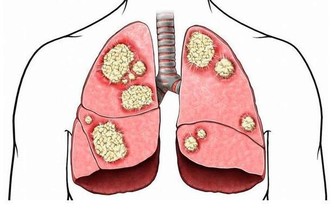

一、肺功能檢查

1、憋氣深吸一口氣,然後憋氣,時間越久越好。能憋氣50秒鐘最理想(50歲為30秒、60歲為25秒),如果少於10秒,說明肺功能很差。

2、吹氣深吸一口氣,然後猛吹氣,能在3秒內吹完則肺功能正常(50歲為4秒,60歲為5秒)。中老年人吹氣時間超過6秒,預示肺功能下降,可能存在氣道阻塞性肺疾患,很可能是慢性阻塞性肺病造成的。